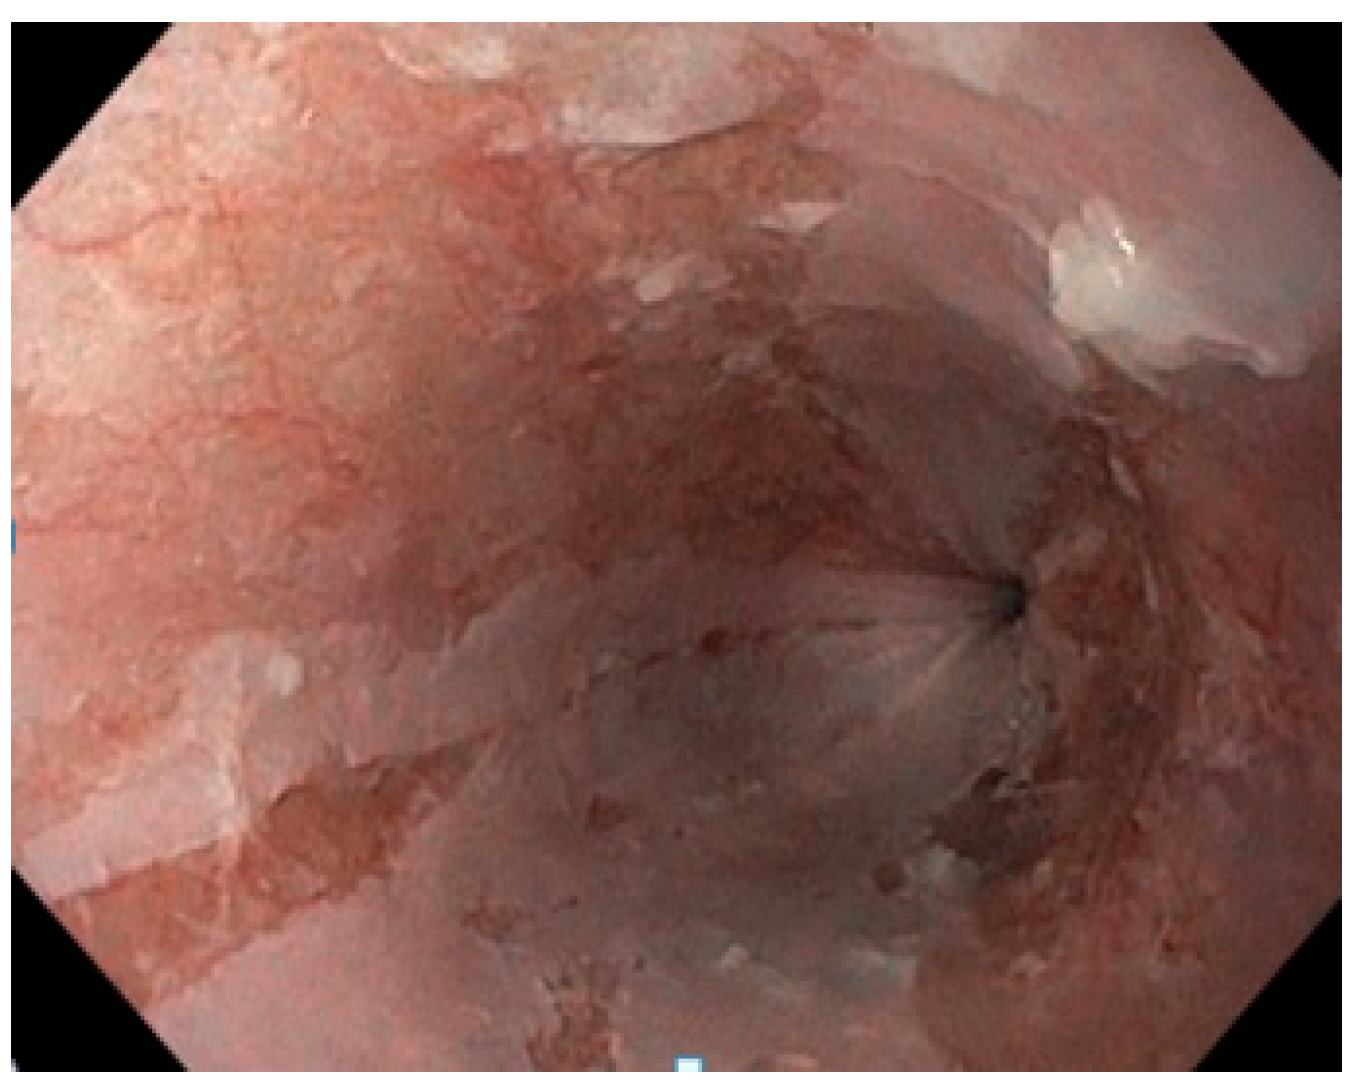

Apixaban-Induced Esophagitis Dissecans Superficialis-Case Report and Literature Review

2. Case Presentation